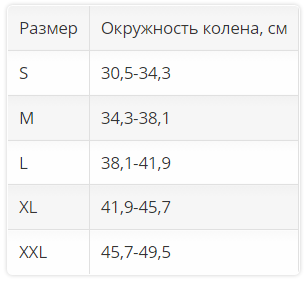

Размер. Для определения размера нужно измерить окружность колена.

| Размер | Окружность колена, см |

| S | 30,5-34,3 |

| M | 34,3-38,1 |

| L | 38,1-41,9 |

| XL | 41,9-45,7 |

| XXL |

45,7-49,5 |